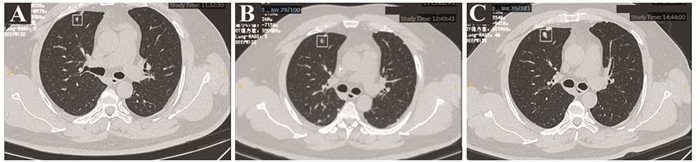

Tetta等[11]在软组织肉瘤肺部结节的恶变率判断中发现临床特征联合CT影像学特点能够展现出更好的预测转归能力。本中心通过对比恶性IPN与良性IPN的胸部CT影像学特征发现,恶性IPN直径平均大小为6.969±1.118 mm,高于良性组,见图 3。这一点与Pontes等[12]研究一致。这也意味着判断良恶性结节最主要的影像学特征首先是其直径,肺部结节的直径越大,结节为恶性的可能性也越大[13]。本研究中,我们发现恶性IPN多为散发、类圆形,多以实性及混合性为主。因此对于伴有IPN的高级别STS患者具有较大的IPN直径、类圆形、实性或混合性可能具有更高的恶变倾向。同时,我们还注意到,治疗后新发的IPN恶性结节的可能性更高。除此之外,IPN发现间期是影响恶性转归的IPN高级别STS患者的独立因素,相较于初筛时发现IPN,治疗后新发的恶性IPN会导致更差的生存,可能与肿瘤细胞对化疗方案耐药有关。因此对于高级别STS患者肺部IPN,我们中心采取根据结节级别分级随访的策略。伴有上述高危因素的合并IPN高级别STS患者推荐每月复查一次胸部CT,直径大于10 mm或出现数量增加后诊断为转移灶,进行早期干预治疗。对于不伴有上述高危风险的合并IPN高级别STS患者推荐每2~3月复查一次,6月后病灶无明显改变,可转为常规随访,见图 4。

![]() 图 3 一例高风险IPN高级别STS患者的胸部CT随访Figure 3 Chest CT follow-up of a patient with high-grade STS and high-risk IPNThis patient was a 46-year-old male diagnosed with high-grade angiosarcoma in left leg. Eight months after the diagnosis of high-grade angiosarcoma, the patient underwent chest CT examination and showed a solid quasi circular nodule that had a clear boundary and a diameter of approximately 7 mm in the middle lobe of the right lung (A). It was included in the high-risk STS IPN follow-up. One month later, chest CT follow-up showed that the diameter of the nodule in the middle lobe of the right lung increased to 10 mm, presenting as a mixed-density nodule with a clear boundary (B). One month later, a follow-up CT scan of the chest revealed that the diameter of the nodule in the middle lobe of the right lung increased to 14 mm, presenting as a full-solid-density nodule with clear boundaries (C). The high-risk IPN was determined as metastatic, and the patient was treated with anlotinib. The patient is currently surviving well.

图 3 一例高风险IPN高级别STS患者的胸部CT随访Figure 3 Chest CT follow-up of a patient with high-grade STS and high-risk IPNThis patient was a 46-year-old male diagnosed with high-grade angiosarcoma in left leg. Eight months after the diagnosis of high-grade angiosarcoma, the patient underwent chest CT examination and showed a solid quasi circular nodule that had a clear boundary and a diameter of approximately 7 mm in the middle lobe of the right lung (A). It was included in the high-risk STS IPN follow-up. One month later, chest CT follow-up showed that the diameter of the nodule in the middle lobe of the right lung increased to 10 mm, presenting as a mixed-density nodule with a clear boundary (B). One month later, a follow-up CT scan of the chest revealed that the diameter of the nodule in the middle lobe of the right lung increased to 14 mm, presenting as a full-solid-density nodule with clear boundaries (C). The high-risk IPN was determined as metastatic, and the patient was treated with anlotinib. The patient is currently surviving well.![]() 图 4 一例低风险IPN高级别STS患者的胸部CT随访Figure 4 Chest CT follow-up of a patient with high-grade STS and low-risk IPNThis patient was a 67-year-old male diagnosed with undifferentiated sarcoma of the left hip joint. Sixteen months after the diagnosis of undifferentiated sarcoma, the patient underwent chest CT examination that showed an irregular, ground glass nodule with a diameter of approximately 5 mm in the anterior segment of the left upper lobe and was included in the low-risk soft tissue sarcoma IPN follow-up (A). Two months later, chest CT follow-up showed that the size and nature of the ground glass nodule in the anterior segment of the left upper lobe were the same as before (B). After three months, chest CT follow-up showed no changes in the size and nature of the ground glass nodule in the anterior segment of the left upper lobe(C). The possibility of metastasis was ruled out, and regular follow-up was conducted every six months.